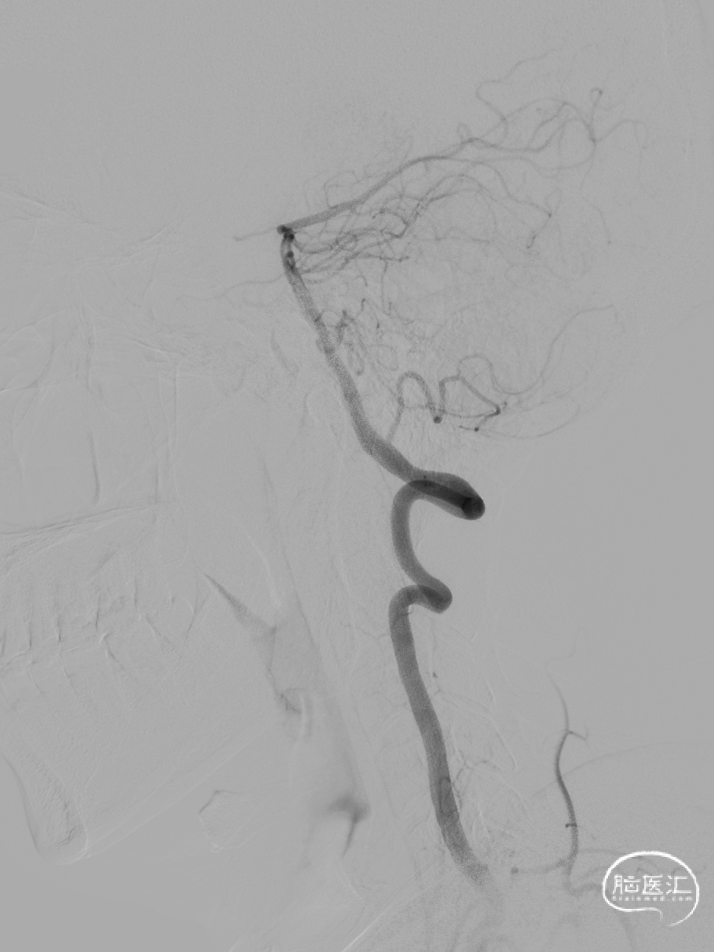

微导管到位:Synchro微导丝引领支架微导管通过病变血管进入大脑中动脉M2段。

支架到位,原位释放,前段打开。

造影确认支架远端打开充分,贴壁良好,继续推送支架。

支架全部释放,调整张力,微导管通过支架,回收输送导丝。

支架内使用成襻微导丝进行按摩,使支架充分贴壁。

术后造影:支架充分覆盖动脉瘤瘤颈,贴壁良好,瘤体内可见造影剂滞留。

术后支架显影:定位精准,未覆盖颞前动脉及大脑前动脉。